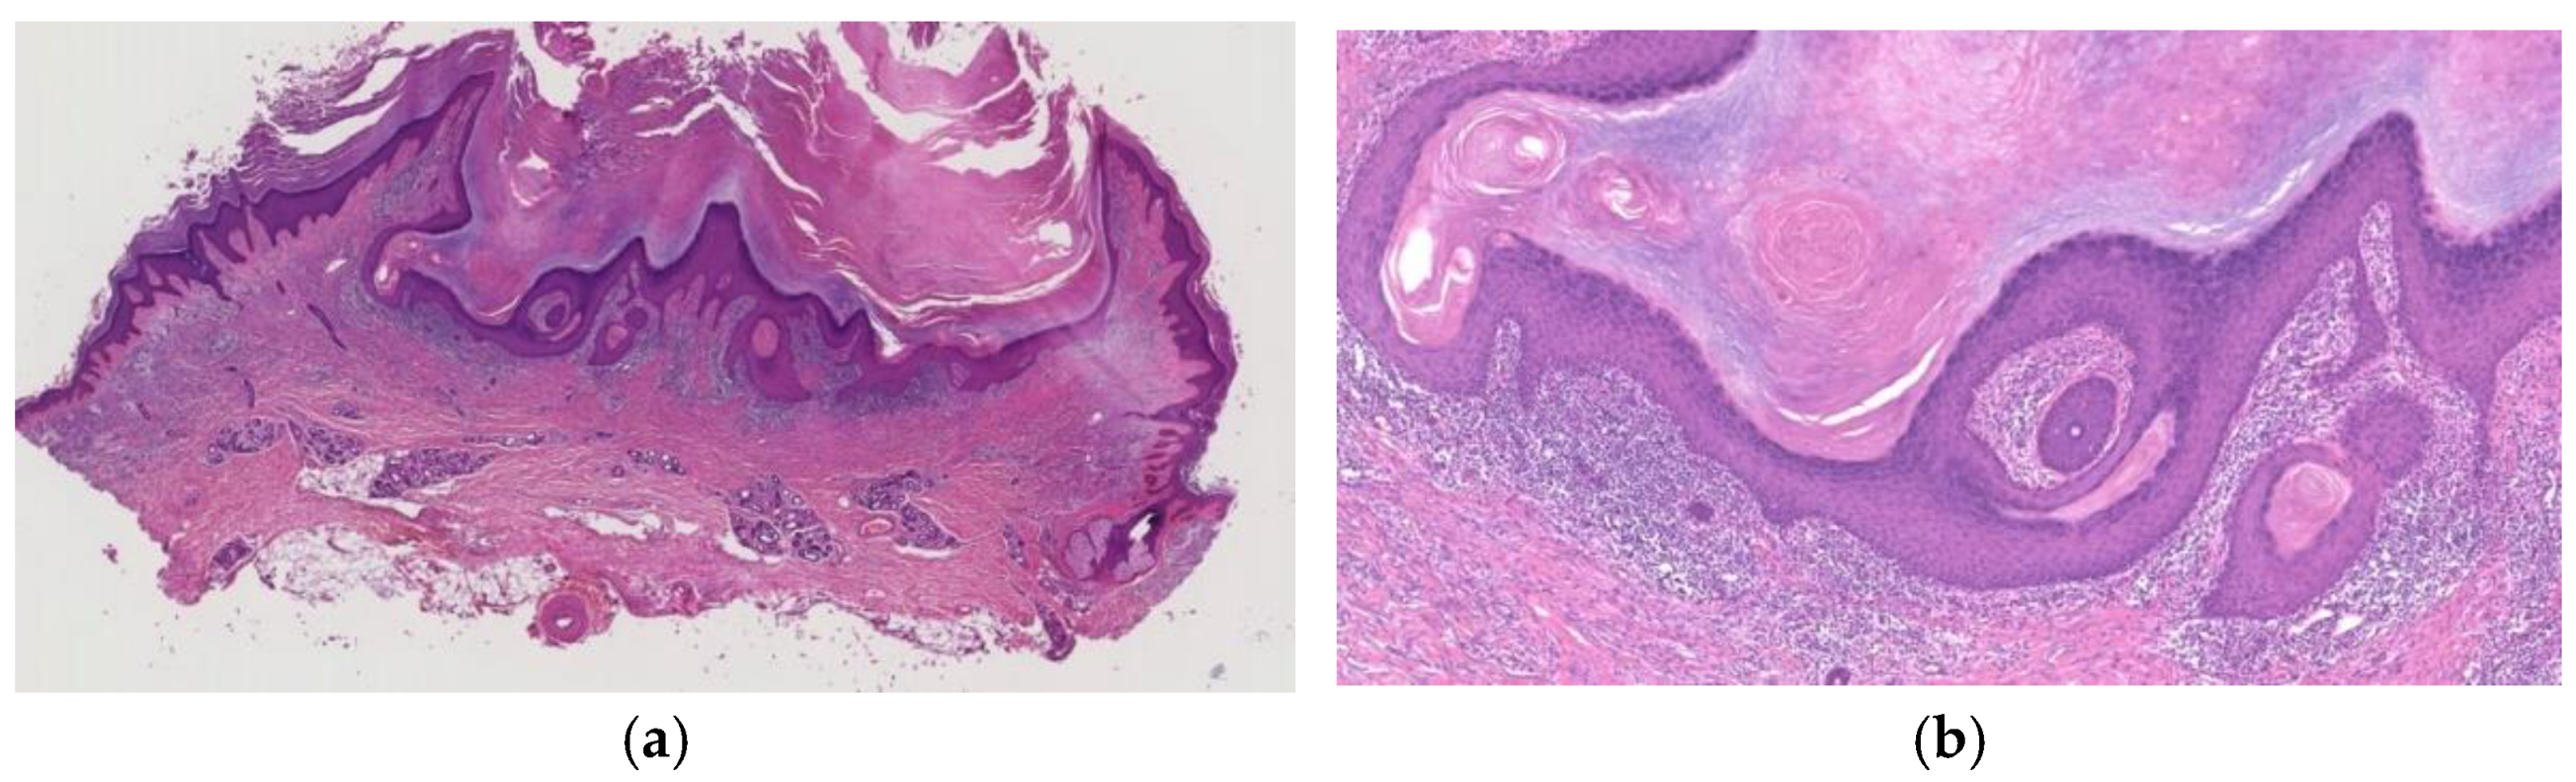

2.2.4. Well-Developed Stage